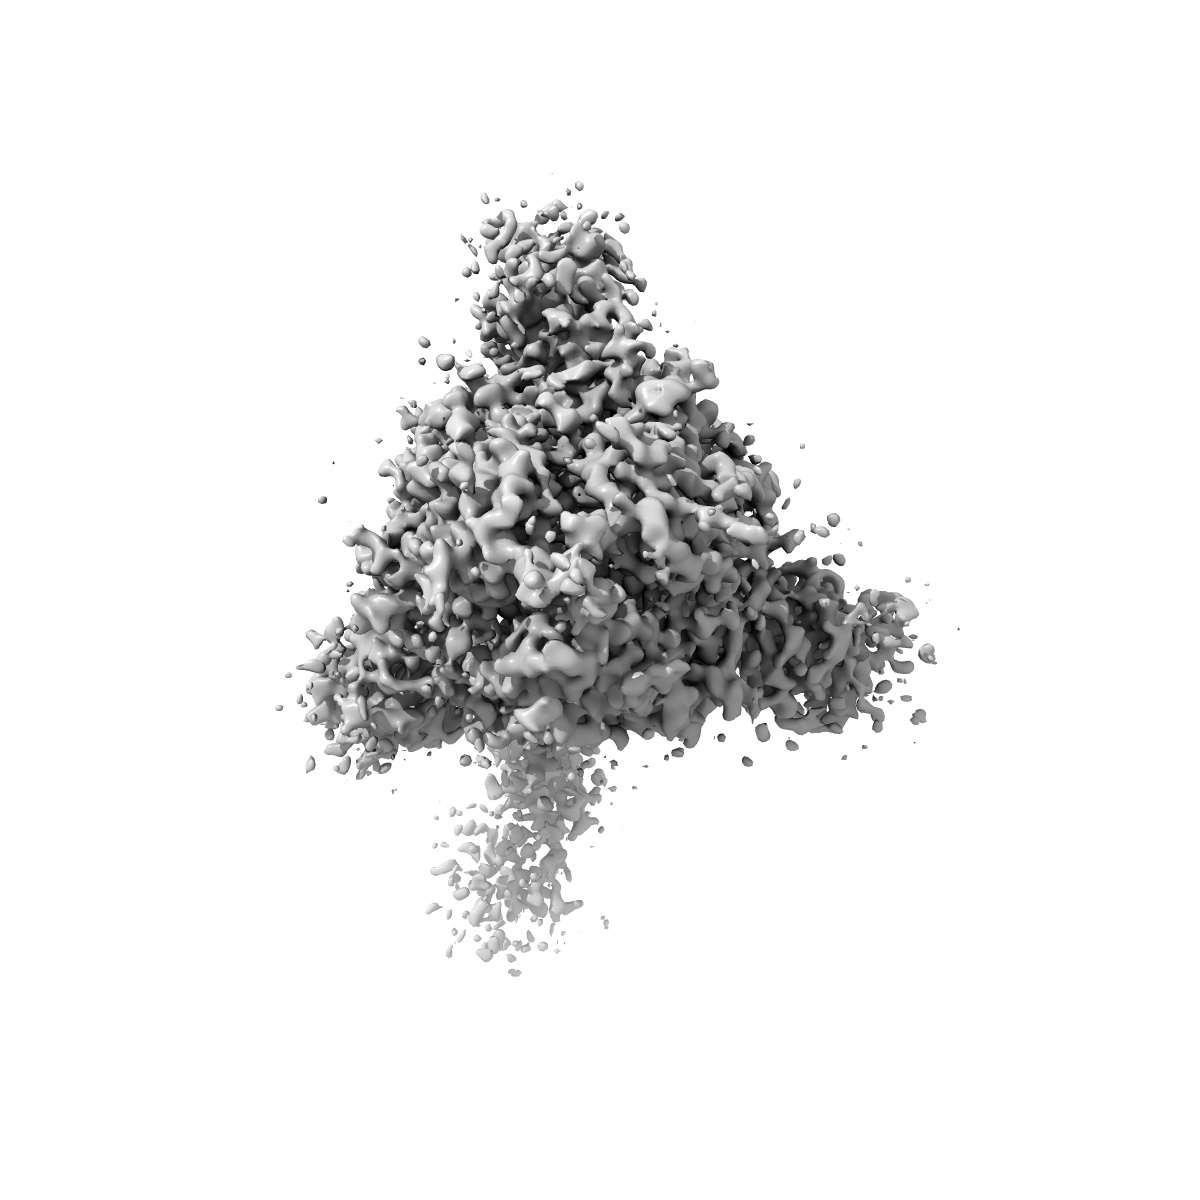

Structure of the SARS-CoV-2 S 6P trimer in complex with the human neutralizing antibody Fab fragment, BG7-15

Single-particle3.7 Å

Sample: Ternary complex of BG7-15 Fab bound to SARS-CoV-2 spike trimer